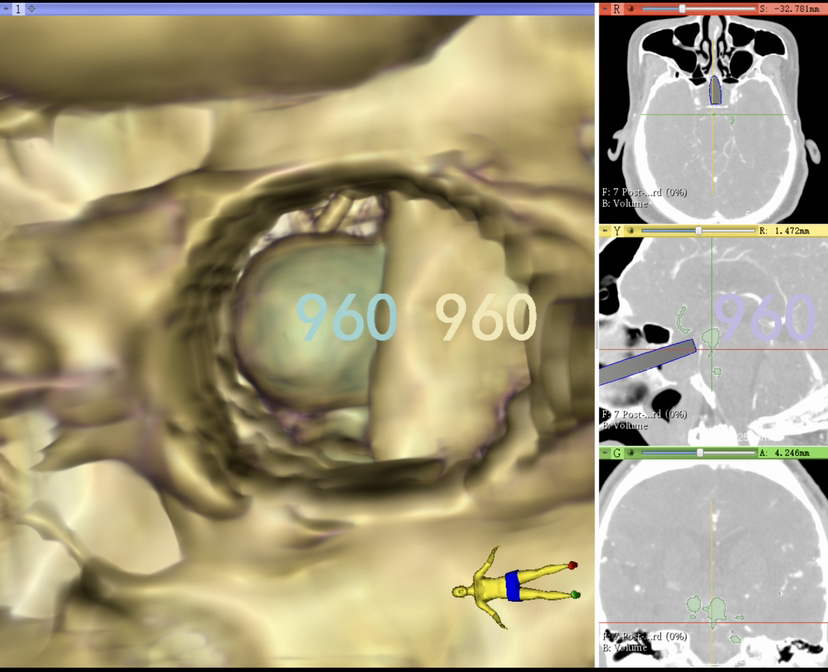

术前规划

制定虚拟内镜术前计划,显示鞍背阻挡动脉瘤颈部。